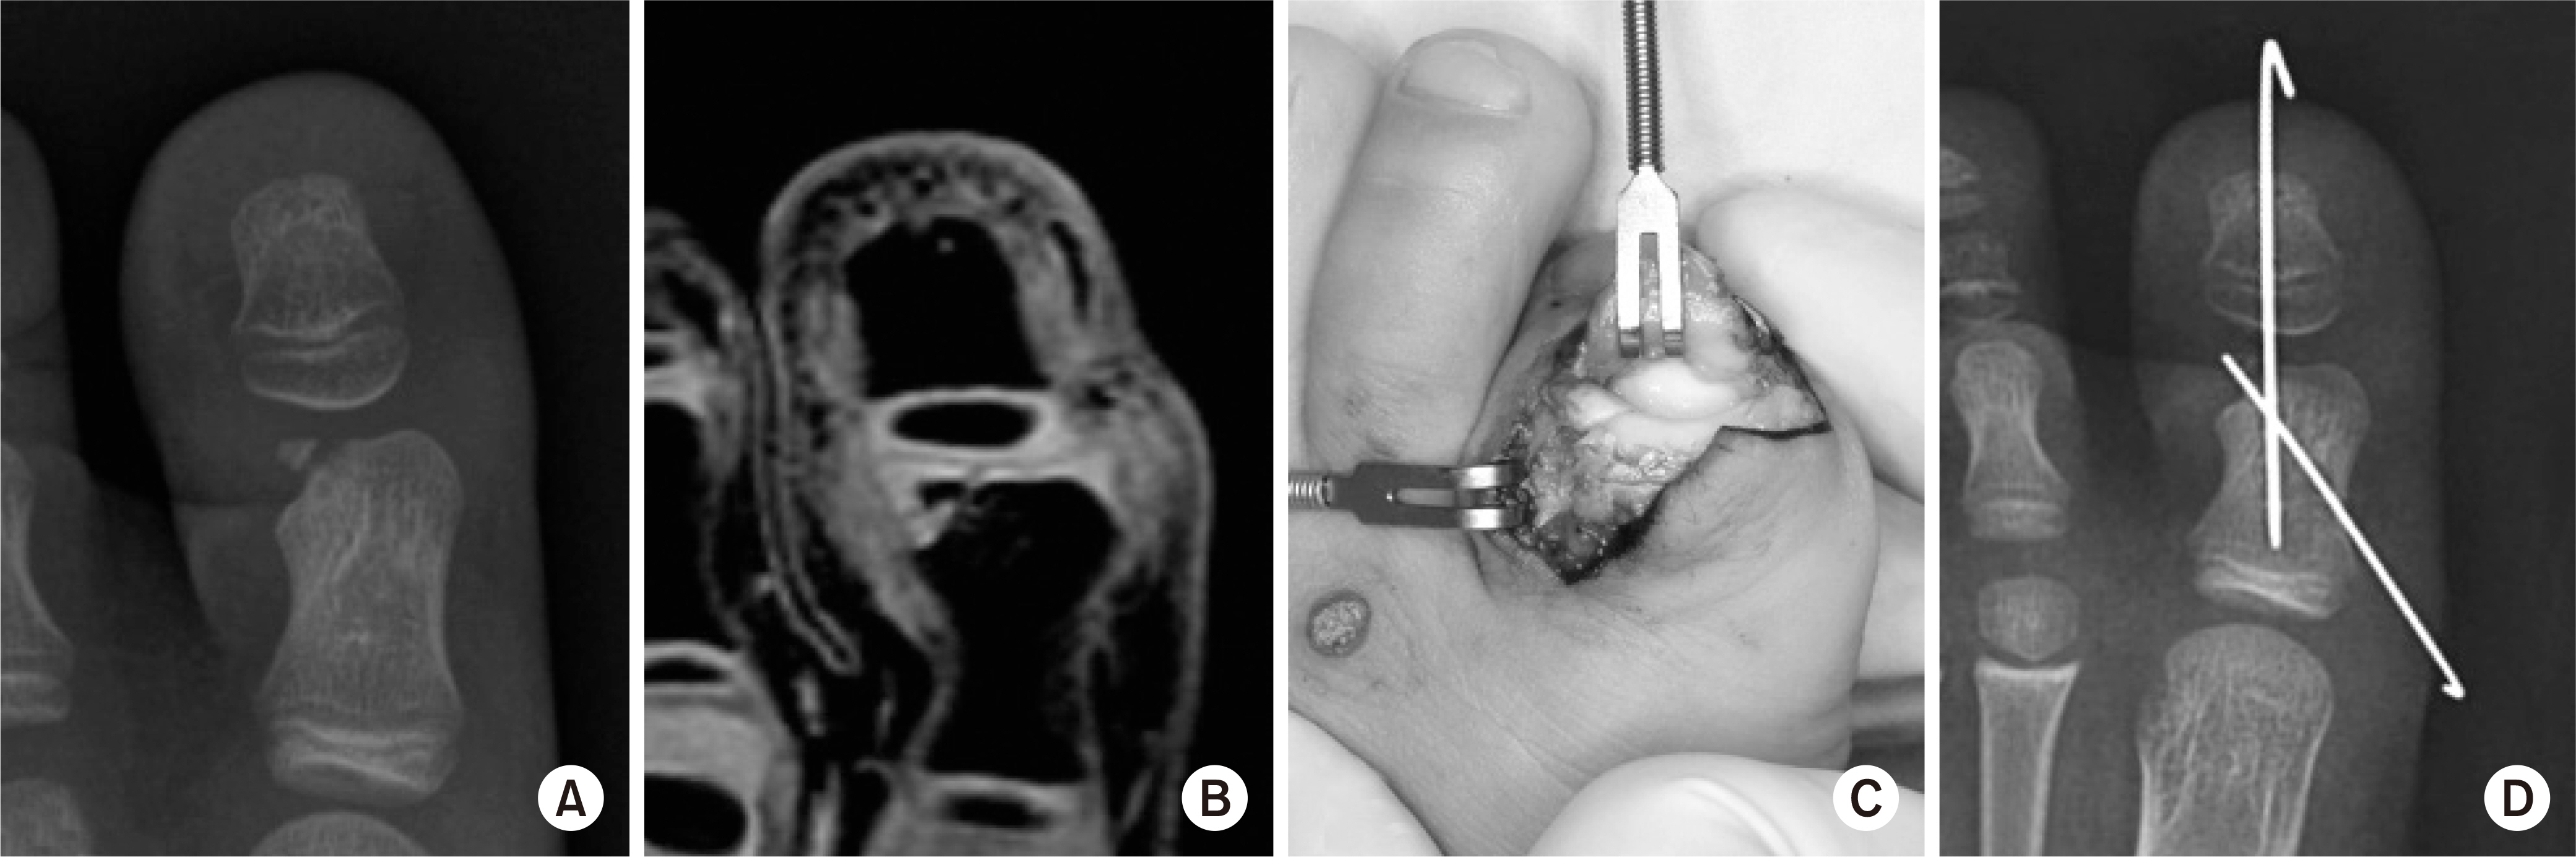

Fig. 5.

(A, B) The size of the osteochondral fragment might be underestimated on the plain X-ray. (C, D) Minimally displaced osteochondral fracture was fixed with two K-wires.